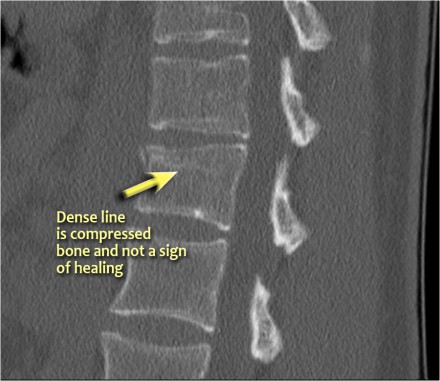

Notice the horizontal band of density, which is often described as sclerosis.

This density does not mean that it involves an older fracture that is already healing with sclerosis.

This is merely a sign of trabecular impaction in an acute fracture.